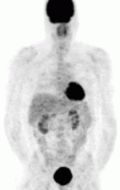

FDG PET — the tumor is appreciated as the dark structure in the patient's left chest. The darkened structure at the head of the patient is the brain, posterior to the abdomen are the kidneys, and in the pelvis is the bladder. These are normal.

Of the four above mentioned modalities, 18F-FDG PET is the most common and readily available functional imaging technique at most hospital systems, but the least-specific to neuroendocrine tumors (Image Left). In 2012, over 200 patients participated in a trial that compared the current gold standard of the time (MIBG/CT/MRI) to the novel FDG PET. Compared to its functional counterpart, FDG outperformed MIBG in detecting soft-tissue and bone metastases with higher specificity in patients with biochemically active tumors.[83]